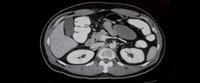

الأشعة المقطعية للبطن هي إحدى الطرق التشخيصية غير الاجتياحية التي تستخدم مجموعة من الصور السينية لإنتاج صورة للبطن ذات دقة عالية. وسنتعرف على الأشعة المقطعية للبطن بشكل أوضح في هذا المقال.

الأشعة المقطعية للبطن: الاستخدامات

تتعدد استخدامات وأهداف الأشعة المقطعية للبطن، ونذكر منها:

البحث عن أي إصابات في البطن بعد التعرض للحوادث.

البحث عن وجود أي انسداد معوي، مع تحديد مكانه.

تحديد سبب وجود ألم أو كتلة في البطن.

الكشف عن سبب وجود دم في البول.

الإصابة ببعض الالتهابات في البطن، مثل التهاب الزائدة الدودية.

نزول الوزن بشكل شديد، دون اتباع أي إجراءات بهدف التنحيف.

تحديد حجم وموقع حصى الكلى.

الأشعة المقطعية للبطن: كيف تتم؟

عادةً ما تستغرق صورة الأشعة المقطعية للبطن فترة تتراوح بين 10 - 30 دقيقة. إذ يقوم الجهاز بأخذ عدة صور أفقية وعمودية للبطن باستخدام الأشعة السينية، حتى يتم التوصل إلى صور أكثر دقة. وتتم الأشعة المقطعية للبطن بالتفصيل باتباع الخطوات الآتية: